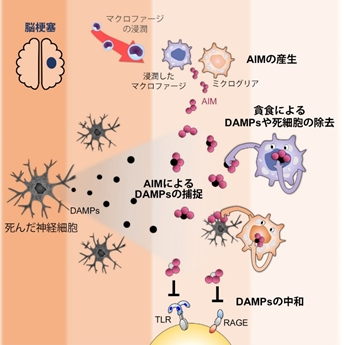

脳梗塞に対するAIMの新しい治療効果の発見

脳梗塞発症に伴い、健常時ほとんど存在しない脳内のapoptosis inhibitor of macrophage(AI...